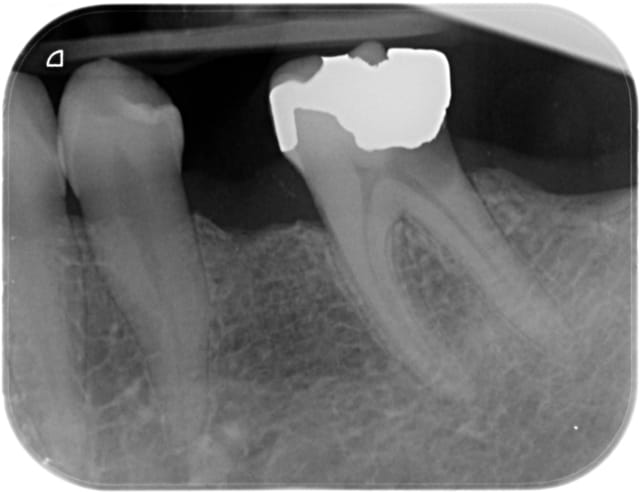

80% du temps, du fuji 2LC (photopolymérisable, avec conditionneur) avec une automatrice (photo 4).

Parfois quand je n'arrive pas à matricer parce que limite trop basse un compo fluide remonté à la main avec mise en place de fil de rétraction dans le sulcus (radios 5 et 6) Mais cela n'est possible que pour un délabrement réduit, une paroi max.

Quand je dépose une couronne/inlay core et que la dent est "à plat", un provisoire (isomoulage) scellé en définitif (fuji plus) après protection au cavit des entrées canalaires. Y a plus qu'à repasser au travers, ça tient très très bien (photos 1,2,3)